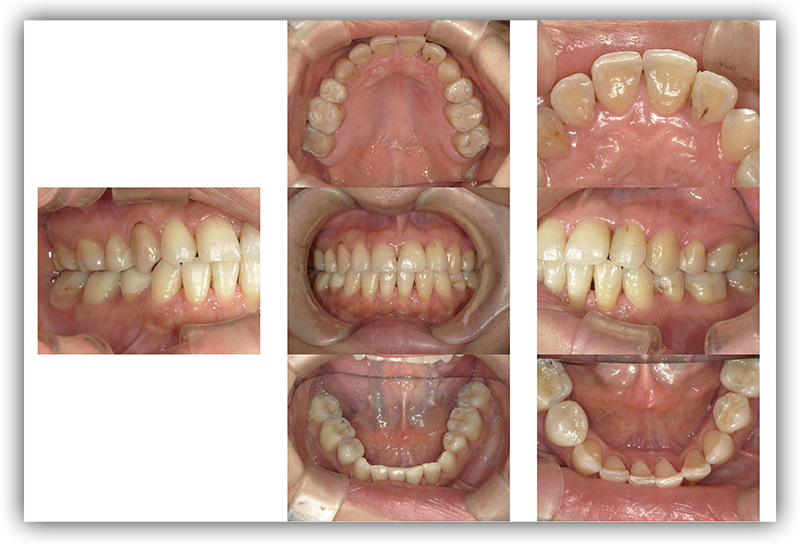

CASE_02

40代男性 セラミック治療

- 患者さん情報(年齢・性別)

- 40代 男性

- 主訴

- 歯を長持ちさせたい。先のことを考えて材質を相談したい。

- 治療箇所

- 9箇所

- 治療方法

- セラミック治療

- 費用

- 約73万円

- 治療期間

- 約半年